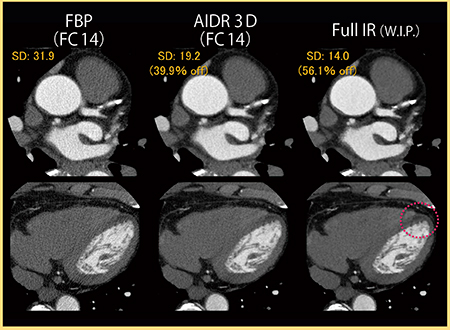

東芝メディカルシステムズでは現在,心電同期に対応したFull IRの開発も進められており,当院にて検討を行った。

図7は,左前下行枝(LAD)起始部の石灰化症例である。FBPやAIDR 3Dでは,石灰化にブルーミングアーチファクトが見られるが,Full IRではほとんど認められず,石灰化の境界も明瞭である。

図8は,陳旧性心筋梗塞症例の冠動脈CTAであるが,Full IRでは血管や臓器の境界がより明瞭である。心尖部には陳旧性の梗塞巣が認められるが,淡い低吸収の梗塞巣の描出能も向上するのではないかと期待している。図9は同一症例のCurved MPR画像であるが,Full IRではノイズ低減に加え,血管や構造物の境界がきわめて明瞭となっている。

100kV,540mA,0.5mm